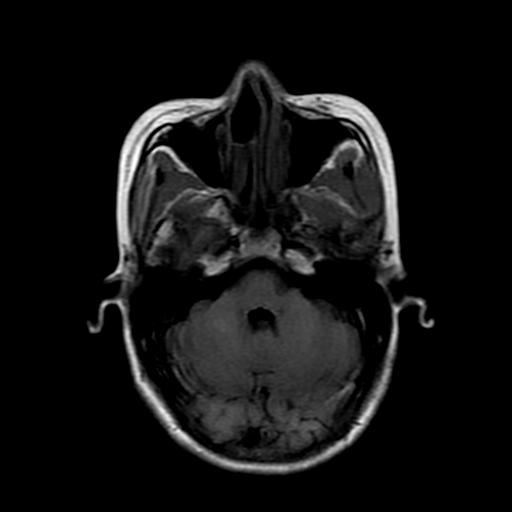

女性,47岁。mri号03027,外伤致头痛9天,抽搐一天,原无类似病史。

dwi及矢状位无明显异常,所以没发。

颞叶前部萎缩,海马萎缩,t2wi海马高信号,支持海马硬化。

双侧海马区t1低,t2高信号。为什么都考虑硬化?发病原因?鉴别诊断:炎症,梗塞等能一下子除外吗?